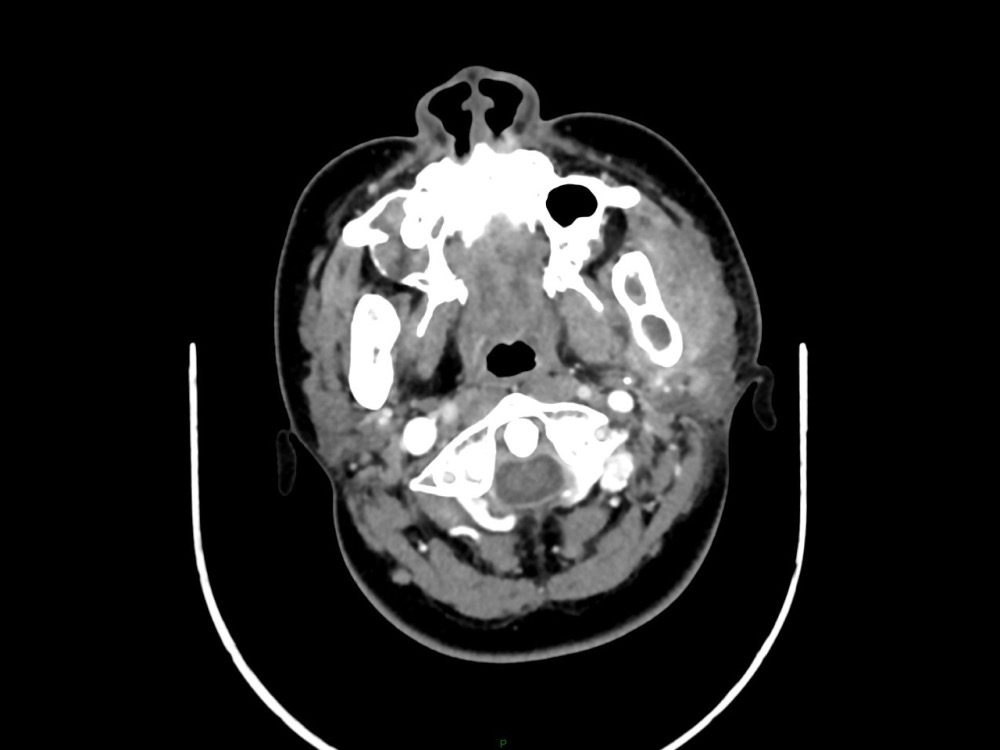

Arsovic / Perrot / Miquel 18/05/2022